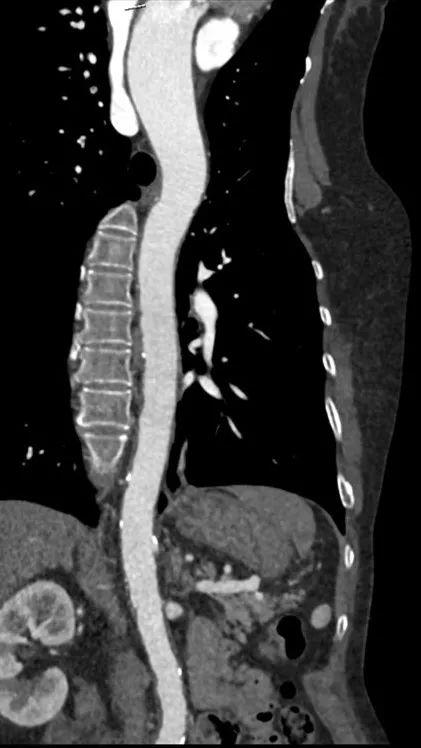

术后1w——冠脉CTA